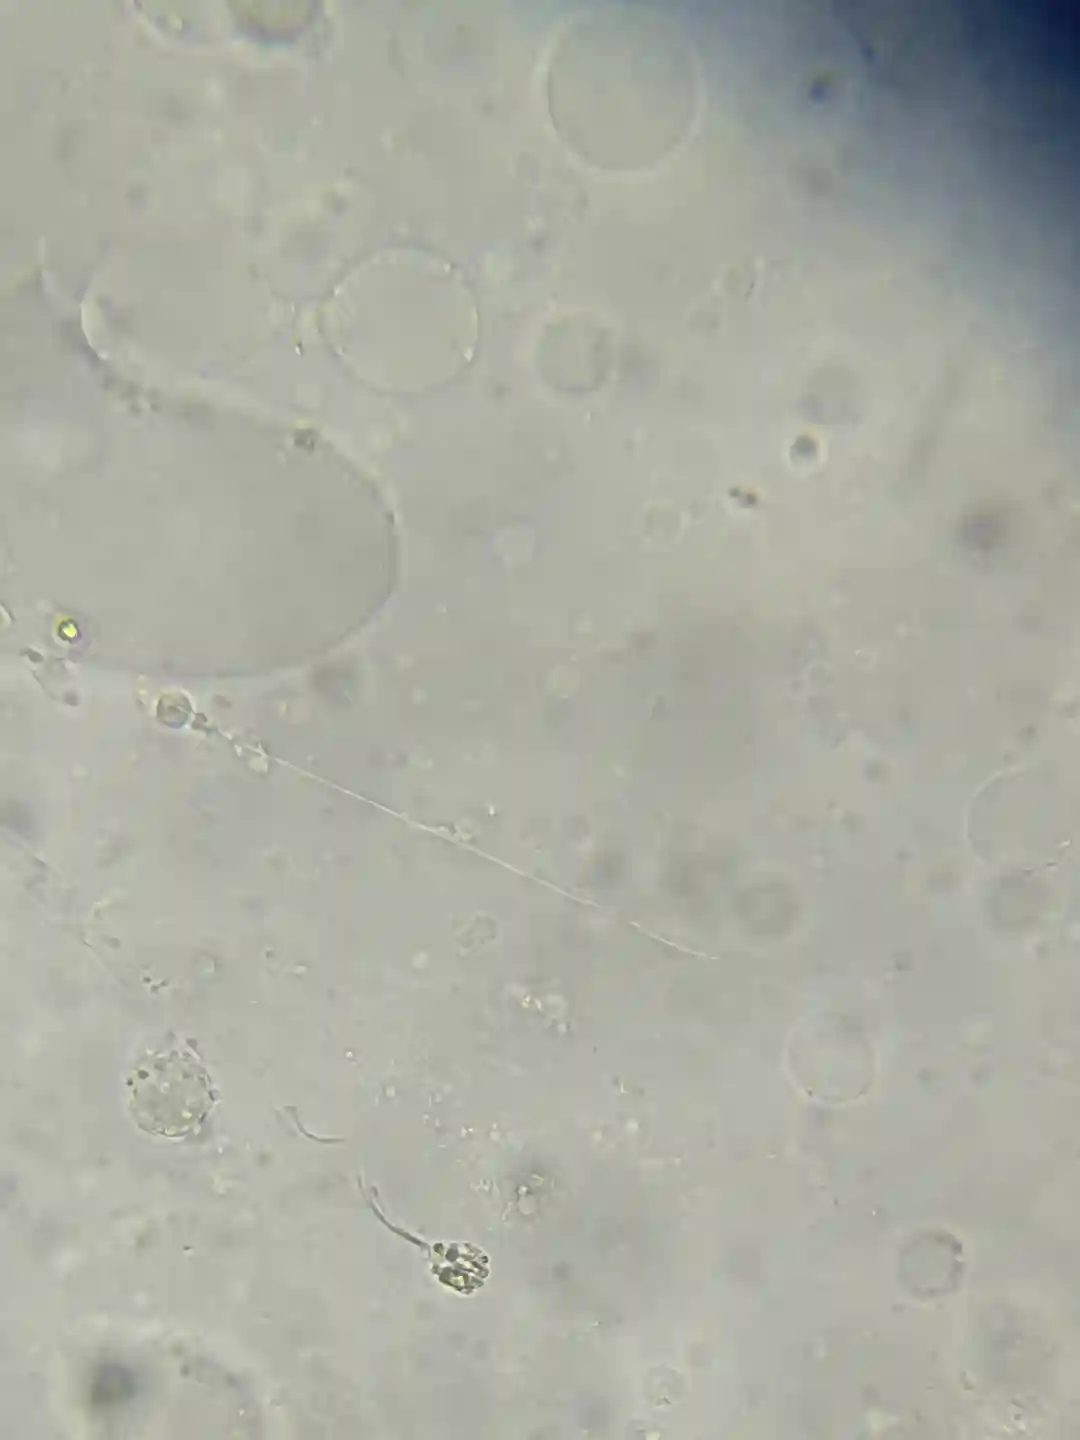

有没有这种情况在做试管的,我老婆一年前去佛山妇幼取卵结果当天无精,然后冻卵跑去中六了。现在基本弃用了,因为感觉那边医生不负责任技术也差。这个月准备取卵了,不知道这种情况做二代有没有希望,张靖医生说他们医院少弱精的成功率都是56%。

染色体没问题,Y微缺失没问题,FSH5-7浮动,🥚🥚大概6.7ml偏小。目前在吃Q10,VE,锌硒片,蕃茄红素,氯米芬片。

小红书里我看到过和我一样的朋友也是单精子冷冻找了几条较好的活动精子做试管然后生了孩子的